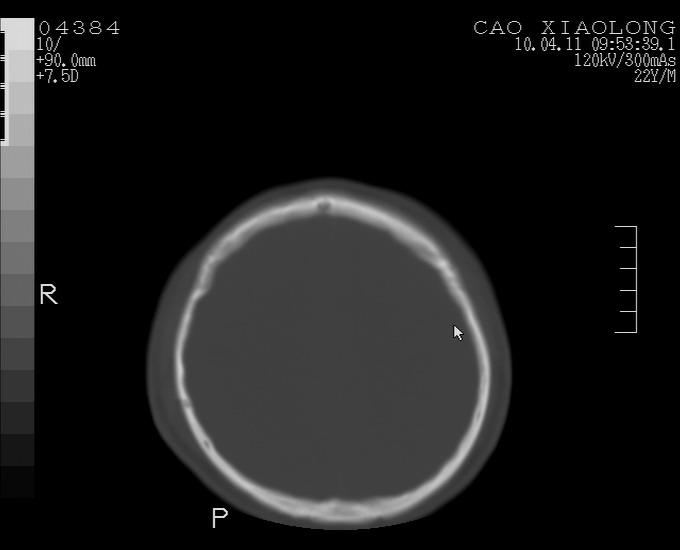

以下是引用随光逐影在2010-4-11 11:00:00的发言:[br]1)左侧额颞顶部硬膜下血肿。2)蛛网膜下腔出血。3)右侧颞顶部颅骨线形骨折。[br][br]20小时后复查:左侧额颞叶脑挫裂伤;左侧额颞顶部硬膜下血肿及蛛网膜下腔出血有吸收表现;右侧颞顶部颅骨线形骨折。[br]